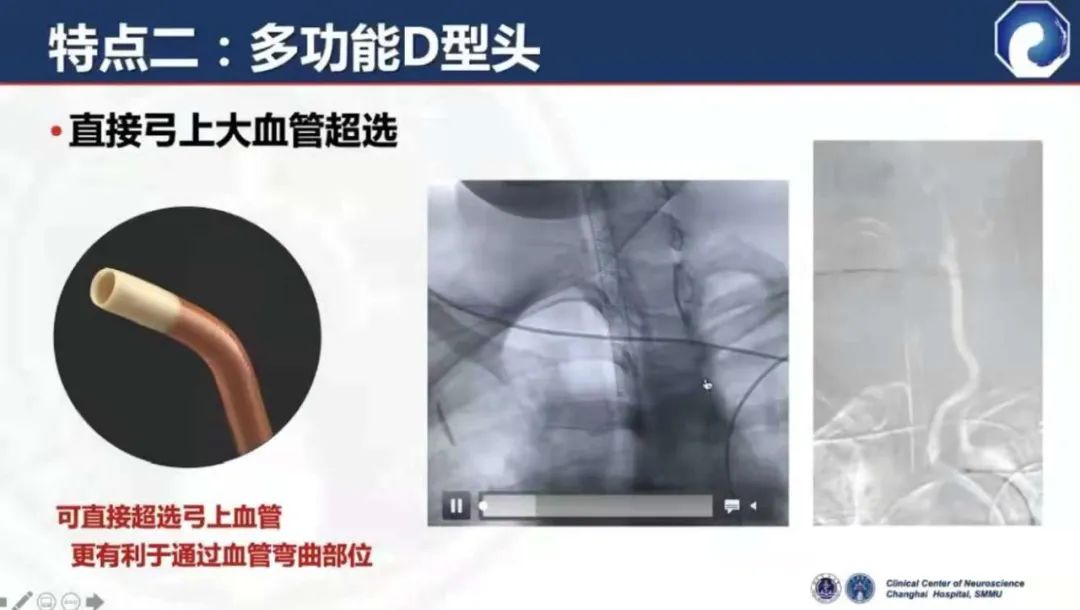

多功能D型头,超选更容易